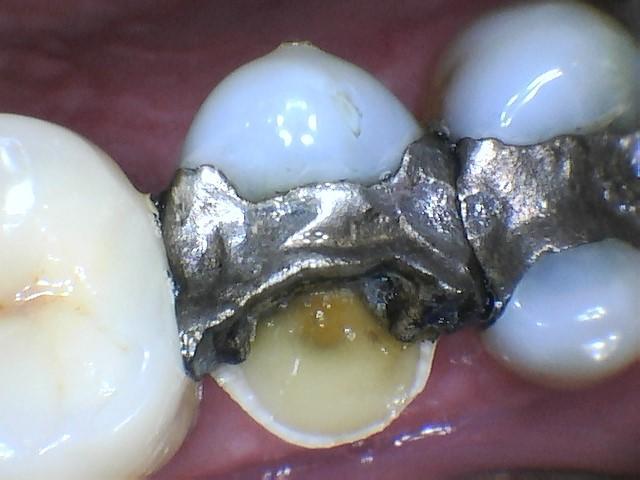

We love using our MouthWatch intra oral camera to document for our patients! We will often use this tool during your appointments to capture an image of older fillings to monitor breakdown, or any other area of the mouth that we want to watch at your next appointment. In this case, our patient came in with a broken tooth caused by an older silver filling, we were able to take an X-Ray of the area along with an intraoral photo to ensure that they received the best next steps for their treatment plan!